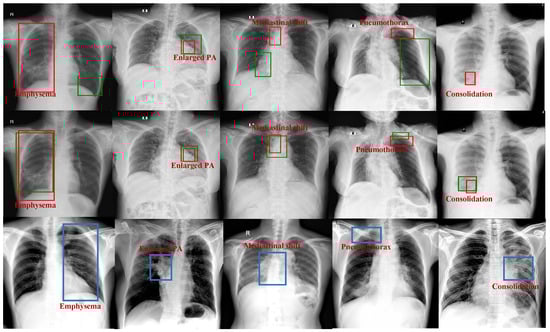

- Due to the instability of the generation process, the generated data contain considerable noise. Therefore, we used a pre-trained medical multimodal model and a trained detection model to filter the generated data.

- Finally, our framework combines the filtered generated data with the original data, effectively improving the detection performance on tail data, and achieving significant enhancements on two benchmarks: VinDr-CXR and RSNA.